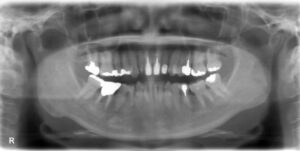

下顎大臼歯3本欠損症例

BEFORE AFTER 60歳男性/下3本欠損/インプラント埋込手術 【治療内容】 左下第一大臼歯は他院で治療中でした…